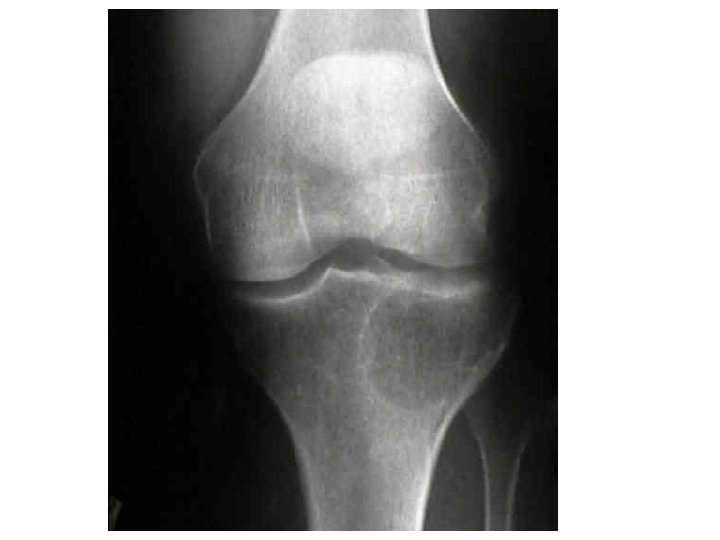

Joints A joint, or articulation, is the place where two bones come together. • Fibrous- Immovable: connect bones, no movement. (skull and pelvis). • Cartilaginous- slightly movable, bones are attached by cartilage, a little movement (spine or ribs). • Synovial- freely movable, much more movement than cartilaginous joints. Cavities between bones are filled with synovial fluid. This fluid helps lubricate and protect the bones.

Types of Joints Hinge- A hinge joint allows extension and retraction of an appendage. (Elbow, Knee)

The Synovial Joint Figure 5. 28 Copyright © 2003 Pearson Education, Inc. publishing as Benjamin Cummings Slide 5. 51